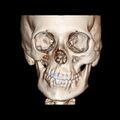

A 3D, soft tissue reconstruction of a CT scan of a 17-year-old girl with Parry Romberg syndrome.

CT scan3D bone reconstruction of a 17-year-old girl with Parry Romberg syndrome.